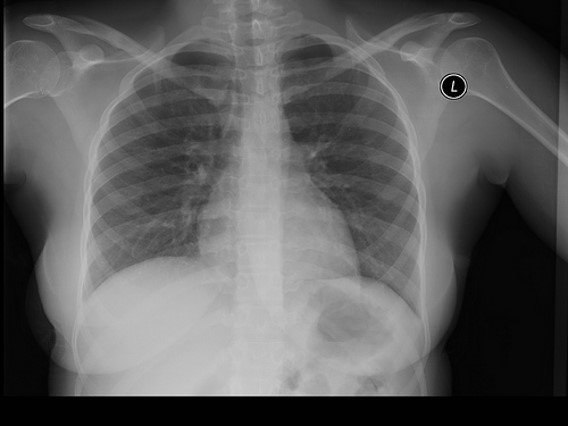

Normal CXR